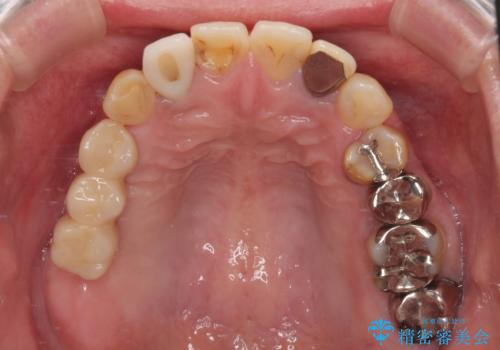

奥歯がしみる オールセラミッククラウンによる奥歯のむし歯治療